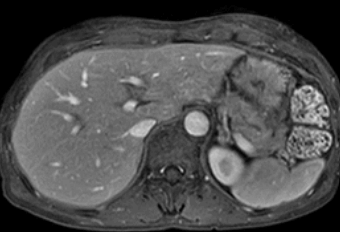

암전문의 김자영 원장이 암 환자의 수술 후 CT 결과에 대해 이야기했어요. 암(癌) 수술 후 CT에서 간전이나 폐전이, 수술 부위 주변 재발 등 생각지 못한 이상 소견을 볼 수 있음을 경험으로 언급했어요.

예를 들어, 대장암 환자의 경우 대장암 수술 후 CT에서 간전이가 발견되는 경우가 많으며, 이는 환자가 의사에게 의문을 제기하는 사례라고 언급했죠. 특히 최장암 환자들 사이에서 이러한 결과가 빈번히 나타날 수 있다고 설명했어요.

4. 암 수술 후 간전이

대장암 수술 후 간전이가 있는 경우, 대장부터 먼저 수술하고 이후 항암치료하는 경우도 있고, 나중에 간전이 된 부위를 수술할 수 있어요.

수술 후 CT 확인 시, 간전이가 크게 성장하거나 개수가 늘어날 수 있지만 이는 수술로 인한 강력한 염증 시그널로 인한 자연적인 반응이에요.

대장암 수술은 몸에 염증을 유발할 수 있지만, 이는 암세포 성장에 직접적인 연관이 있다기보다는 시그널에 반응하는 세포들이 빨리 성장할 수 있다는 것을 의미하는 거죠.

따라서 대장암 수술 자체가 암세포 성장을 촉진하는 것은 아니며, 갑자기 빠르게 암이 성장하는 것은 자연적인 반응이라는 점을 이해해야 해요.